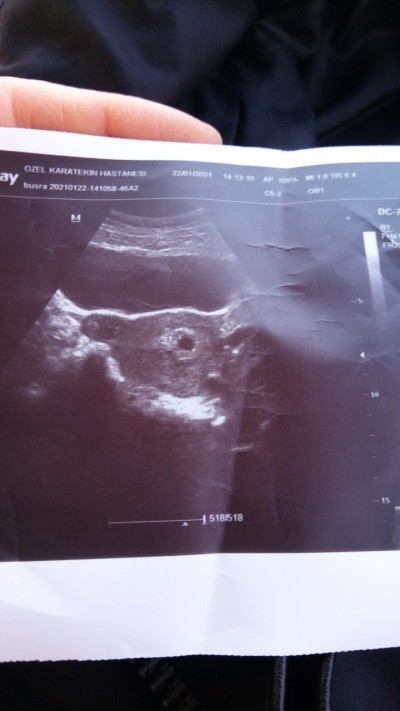

Kızlar merhaba. Aralık ayında kimyasal gebelik geçirdim. Hiç adet olmadan hamile kaldım. Normalde 5+5 olması gerekirken 4+5 olduğunu geç döllenme olduğunu söyledi doktor. Sadece kese gözüktü. Haftada 1 lekelenmelerim oluyor. Bu normal bişey mi geç döllenme herhangi bi sorun çıkarır mı ?  4+5 kese görüntüsü de bu şekilde

Gebelik haftası 4+5